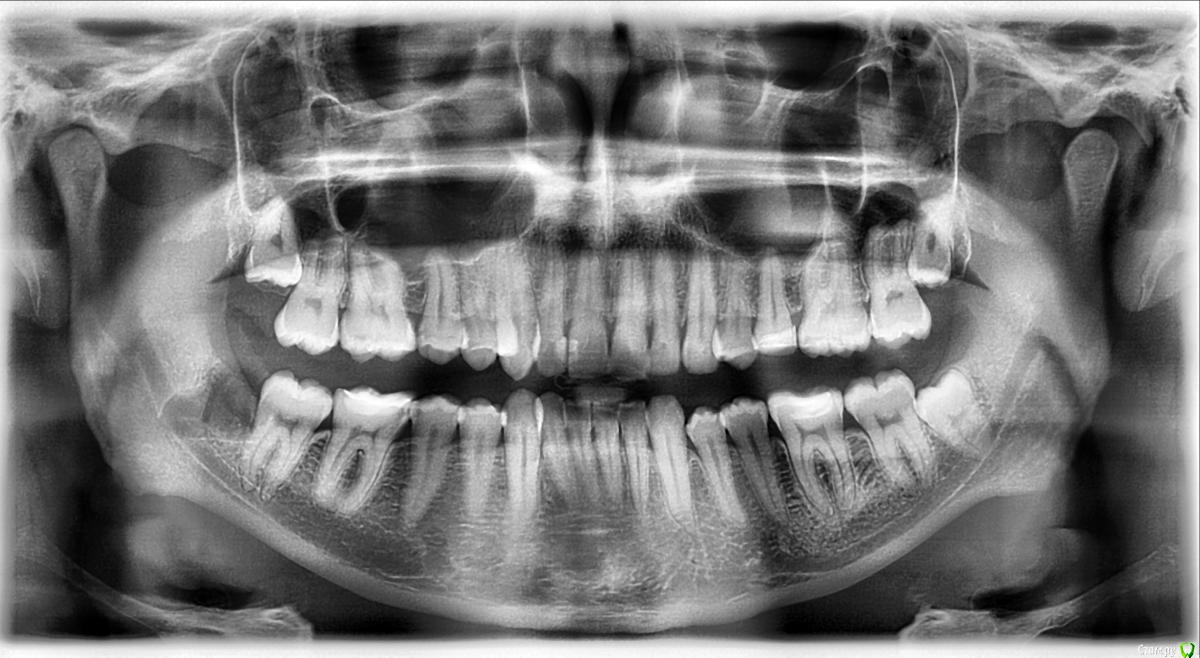

vano-box Опубликовано 2 августа, 2016 Поделиться Опубликовано 2 августа, 2016 Здравствуйте, подскажите мне пожалуйста, пару месяцев назад начали беспокоить небольшие боли в районе 6-7 зуба снизу справа, стоматолог после рентгена этих зубов сказал, что с 6 и 7 всё норм и посоветовал обратиться к лору. В итоге на неделе я сам сделал панорамный снимок и увидел там, что восьмерка лежит на боку и давит на соседний зуб, я так понимаю, что её нужно удалять, не могли бы Вы подсказать мне насколько сложное предстоит удаление, не знаю как лучше удалить во сне или под местной анастезией? Просто одно дело удаление в течении часа, но в интернете прочитал, что у кого то это занимало 2 часа, плюс дотоло и молоток, выпиливание и т.д., а такая перспектива удаления когда я буду сознании мягко говоря не привлекает. Что мне лучше выбрать? Ссылка на комментарий

red_butler Опубликовано 2 августа, 2016 Поделиться Опубликовано 2 августа, 2016 Зубы как зубы, если удалять под седацией, то все четыре сразу. Молоток, долото, и прочий строй инструмент не нужны )))Плюс нужно посмотреть/исключить пульпит в 3.6 зубе Ссылка на комментарий

vano-box Опубликовано 10 сентября, 2016 Автор Поделиться Опубликовано 10 сентября, 2016 Доброй ночи. Мажу метрогилом, но пока как то без улучшений, уже 10 день после удаления, а ноет всё равно, разве должно так долго болеть? Сегодня сделал фото лунки, и сделал ортопанораму, скажите там всё нормально?И ещё если трогать щеку беспокоит твердая болезненная гематома, сколько она заживает в среднем? Ссылка на комментарий

red_butler Опубликовано 11 сентября, 2016 Поделиться Опубликовано 11 сентября, 2016 а ноет всё равно, разве должно так долго болеть? а как болит? На семерке похоже пульпит.за операционной областью или стоматит или оголенная кость, попробуйте попасть к другому врачу Ссылка на комментарий

vano-box Опубликовано 14 сентября, 2016 Автор Поделиться Опубликовано 14 сентября, 2016 Продолжение моей истории, был у своего доктора 12-го в понедельник, посмотрев гематому он сказал, что у меня начался процесс абсцедирования, вскрыли гематому (или это уже абсцесс не знаю) и поставили дренаж, шишка в щеке уменьшилась, стала помягче, перестала быть такой болезненной, но до конца пока не прошла, пью амоксиклав 625мг+диазолин. Собственно, что меня волнует:1. Исходя из моих снимков мог ли этот абсцесс образоваться из за инфекции в 4.6 или в 4.7 зубе? Просто ноющие боли в этих зубах продолжаются, хотя после вскрытия и установки дренажа они заметно снизились, но я почему то "втираю" себе, что все мои проблемы в одном из этих зубов. Я собственно говоря и удалил 4.8 потому, что у меня справа внизу были боли незначительные полгода(боли начались после того как мне на отколовшийся кусочек пломбы на 4,6 поставили заплатку), но два терапевта сказали мне, что виновник боли - зуб мудрости. И вот зуба нет, а проблемы остались.2 Что мне делать, что бы не началось лечение всего рта в поисках источника или подождать заживления абсцесса и ничего пока не делать? Ссылка на комментарий

red_butler Опубликовано 14 сентября, 2016 Поделиться Опубликовано 14 сентября, 2016 1. Исходя из моих снимков мог ли этот абсцесс образоваться из за инфекции в 4.6 или в 4.7 зубе? не похоже 2 Что мне делать, что бы не началось лечение всего рта в поисках источника или подождать заживления абсцесса и ничего пока не делать? когда заживет, санируйте полость рта и удаляйте остальные "восьмерки" Ссылка на комментарий